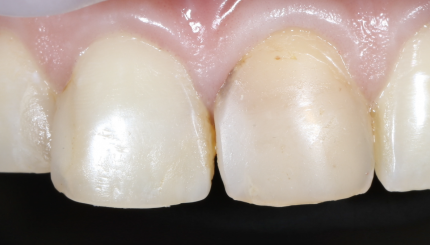

Предварительное препарирование 12 11 21

10 августа 2021